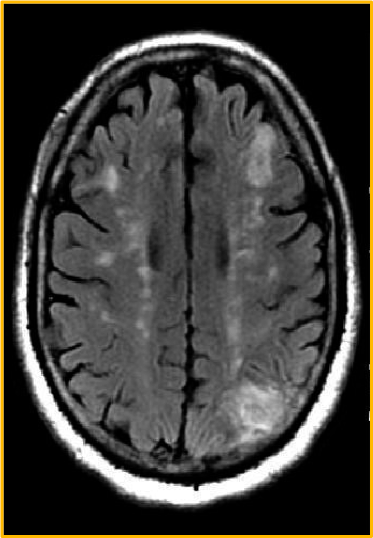

Deep border-zone, or watershed infarcts

MRI scan of a 62-year-old man with HTN and diabetes and a history of transient episodes of right-sided weakness and aphasia. The FLAIR image demonstrates patchy areas of high signal arranged in a linear fashion in the deep white matter, bilaterally. This configuration is typical deep border-zone, or watershed infarction, in this case the anterior and posterior middle cerebral artery (MCA)